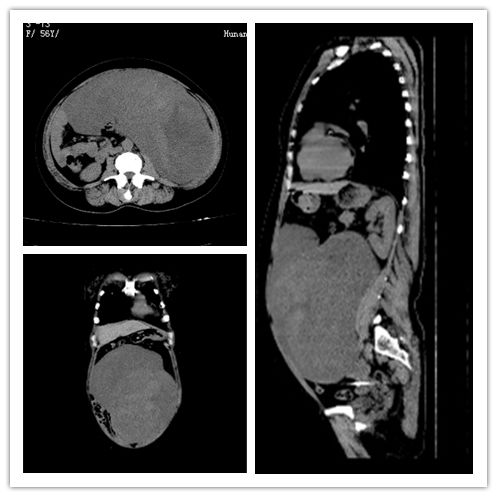

ct提示腹膜后巨大肿瘤。

通过多项检查诊断技术全面评估了肿瘤的部位、与周围脏器及血管关系、性质、可能来源及患者全身状况,发现肿瘤具有恶性征象,位于左侧髂内外血管之间,左侧髂外动脉向前移位,髂内动脉向后移位,左侧的升结肠、乙状结肠被挤压到了右侧。由于肿瘤部位特殊,与周围脏器、组织及血管关系密切,手术难度极高。在学科顾问黄忠诚教授、科主任肖志刚教授的带领下,科室组织多次讨论,制定了术前处理、手术切除、术中监测、术后治疗和康复方案。

经过精心的术前准备,58日,肖志刚、谭浩翔等克服重重困难,成功切除患者腹膜后的巨大肿瘤,出血量不足50ml,测量肿瘤有29*28*9cm大小,重达10余斤。由于术中的精细解剖,患者重要脏器血管均未受损,手术效果超过术前预期。